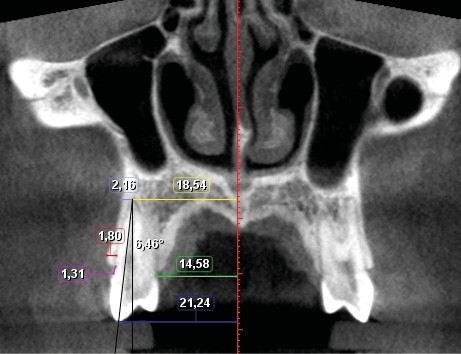

Fig. 2 - Coupe frontale montrant les mesures effectuées sur un cas.

Sept mesures ont été réalisées pour quantifier le déplacement dentaire et les modifications alvéolaires (fig. 1 et 2). de chaque côté :

– largeur au niveau de l’apex ;

– largeur palatine mesurée au niveau du collet ;

– largeur au niveau de la cuspide vestibulaire ;

– quantité de version ;

– épaisseur de l’os alvéolaire à l’apex ;

– épaisseur de l’os alvéolaire coronaire mesurée à 2 mm apicalement à la crête ;

– distance jonction amélo-cémentaire-crête alvéolaire.